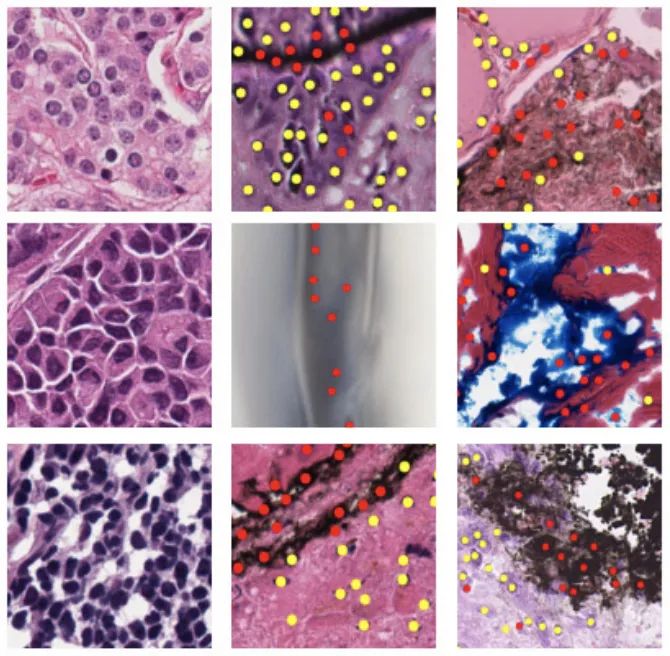

结直肠腺癌组织学图像数据集

数据集链接:http://m6z.cn/6axBLk

该数据集包含 100 张 H&E 染色的结直肠腺癌组织学图像。出于检测目的,在中心/周围共标记了 29,756 个原子核。其中,有 22,444 个细胞核也具有相关的类别标签,即上皮细胞、炎症细胞、成纤维细胞和其他细胞核。